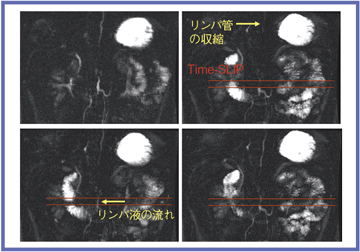

●リンパ管への応用

リンパ管は,腹腔内のリンパを集めて乳糜槽をつくる。乳糜槽内を流れるリンパ液は乳糜槽の拡張収縮により上行するため,乳糜槽径は経時的に変化することが知られている。

MRIで乳糜槽の収縮拡張に伴う径の経時的変化を見ると,2mm以上の変化が正常群では11%,肝硬変群では18%に見られた。Time-SLIPを用いてリンパ管を観察したところ,リンパ液の流れによって,乳糜槽の収縮拡張や,胸管の径が変化する様子がとらえられた(図8)。